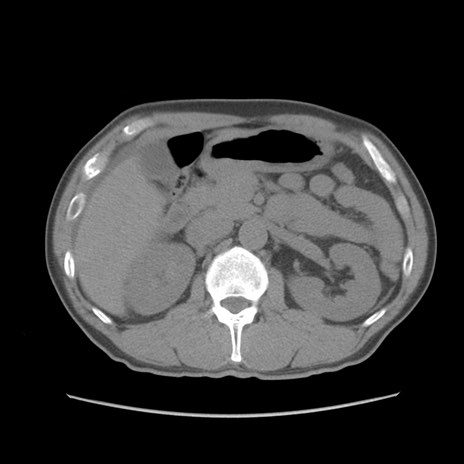

症例56 CT(横断像)

脂肪ウインドウ